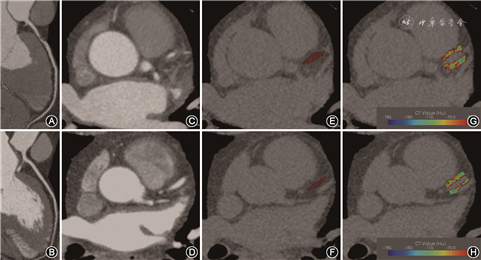

2. 冠周脂肪勾画分割:首先通过CCTA的曲面重建(CPR)图像确定病变组与对照组的冠状动脉情况(图1A、1B),再观察CCTA横断位图像中冠状动脉开口10~50 mm范围的冠状动脉(图1C、1D),之后采用Perivascular Fat Analysis Tool软件(中国数坤科技有限公司)勾画纳入的每一例患者CCS图像上的左右冠状动脉(图1E、1F),左冠状动脉以左主干起始,从冠状动脉开口处10 mm出发至左前降支,连续勾画40 mm;右冠状动脉从开口处10 mm出发,连续勾画40 mm,左回旋支因其走形迂曲并且周围脂肪较少,不予评估[5]。病变组勾画纳入的每一支冠状动脉;对照组统一勾画每一例患者的左右冠状动脉。勾画完毕后,使用Perivascular Fat Analysis Tool软件的Fat Segmentation功能,自动生成冠周的脂肪(CT值范围:-190~-30 HU)(图1G、1H)。